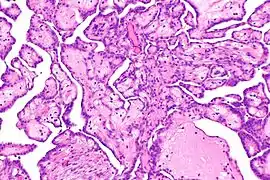

- Carcinome : la majorité des cellules cancéreuses sont d'origine épithéliale, nées dans les tissus qui enveloppent les organes.

Cellules de carcinome.